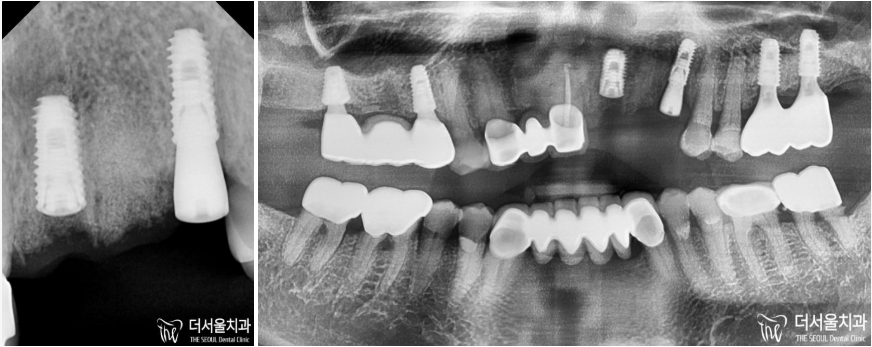

이분께서 앞니가 부러져서 빠졌다고 오셨기에

말씀하신 내용을 토대로 확인을 했습니다.

어.. 한 군데가 아닌,

왼쪽 앞니 두 곳에 부러짐이 나타나 있네요.

이와 더불어,

주변에 있는 치아들도 상황이 좋지 않았습니다.

아무래도 단순히 부러진 것이 아니라는 판단이 들어

정확한 진단을 위해 엑스레이 촬영을 진행했습니다.

그 결과.. 뼈까지 손상이 생겨있는 것을 확인할 수 있었죠.

아.. 이런 경우에는 치아만 뺀다고 해서 될 문제가 아닙니다.

단순히 치아만 파절 되었다면 비교적 간단하게 해결할 수 있지만

이렇게 뼈에도 문제가 생긴 경우에는 그렇지 못하죠..

치조골 소실도 심한 상태였기에

더서울에서는 뼈이식을 동반한 임플란트 로

치아 부러짐 및 상황이 좋지 않은 송곳니까지

개선을 도와드리기로 했습니다.